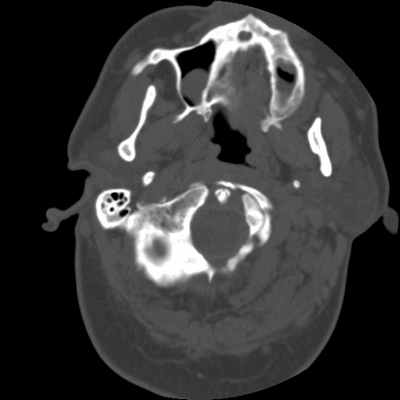

Не стоит забывать и о Ecchordosis physaliphora* (Клин. наблюдение 3). Это врожденная доброкачественная гамартома, которая формируется из нотохордальных зачатков и может встречаться в любой кости, начиная от основания черепа, оканчивая крестцом. Как правило, протекает бессимптомно и является случайной находкой при проведении КТ или МРТ. Выглядит как дефект ската, четко отграниченный и с гладкими контурами, без агрессивного компонента [5]. В литературе описан случай симптомного течения Ecchordosis physaliphora [6], однако, это, скорее, исключение из правил.